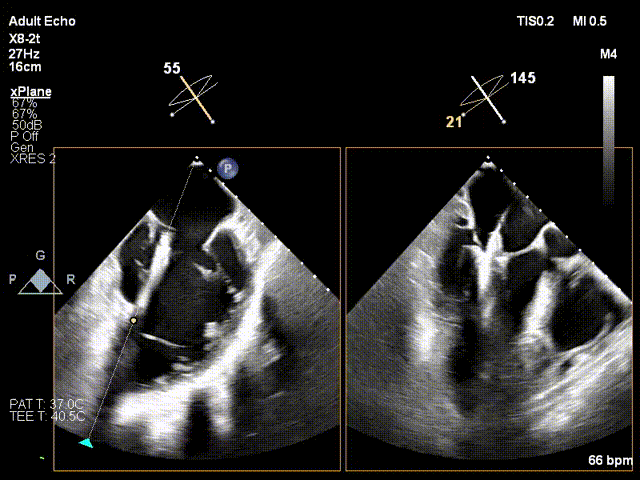

两枚夹子中间有残余反流1+

解离后3D评估组织桥稳定

反流未增加

TMPG:1mmHg

肺静脉逆流消失